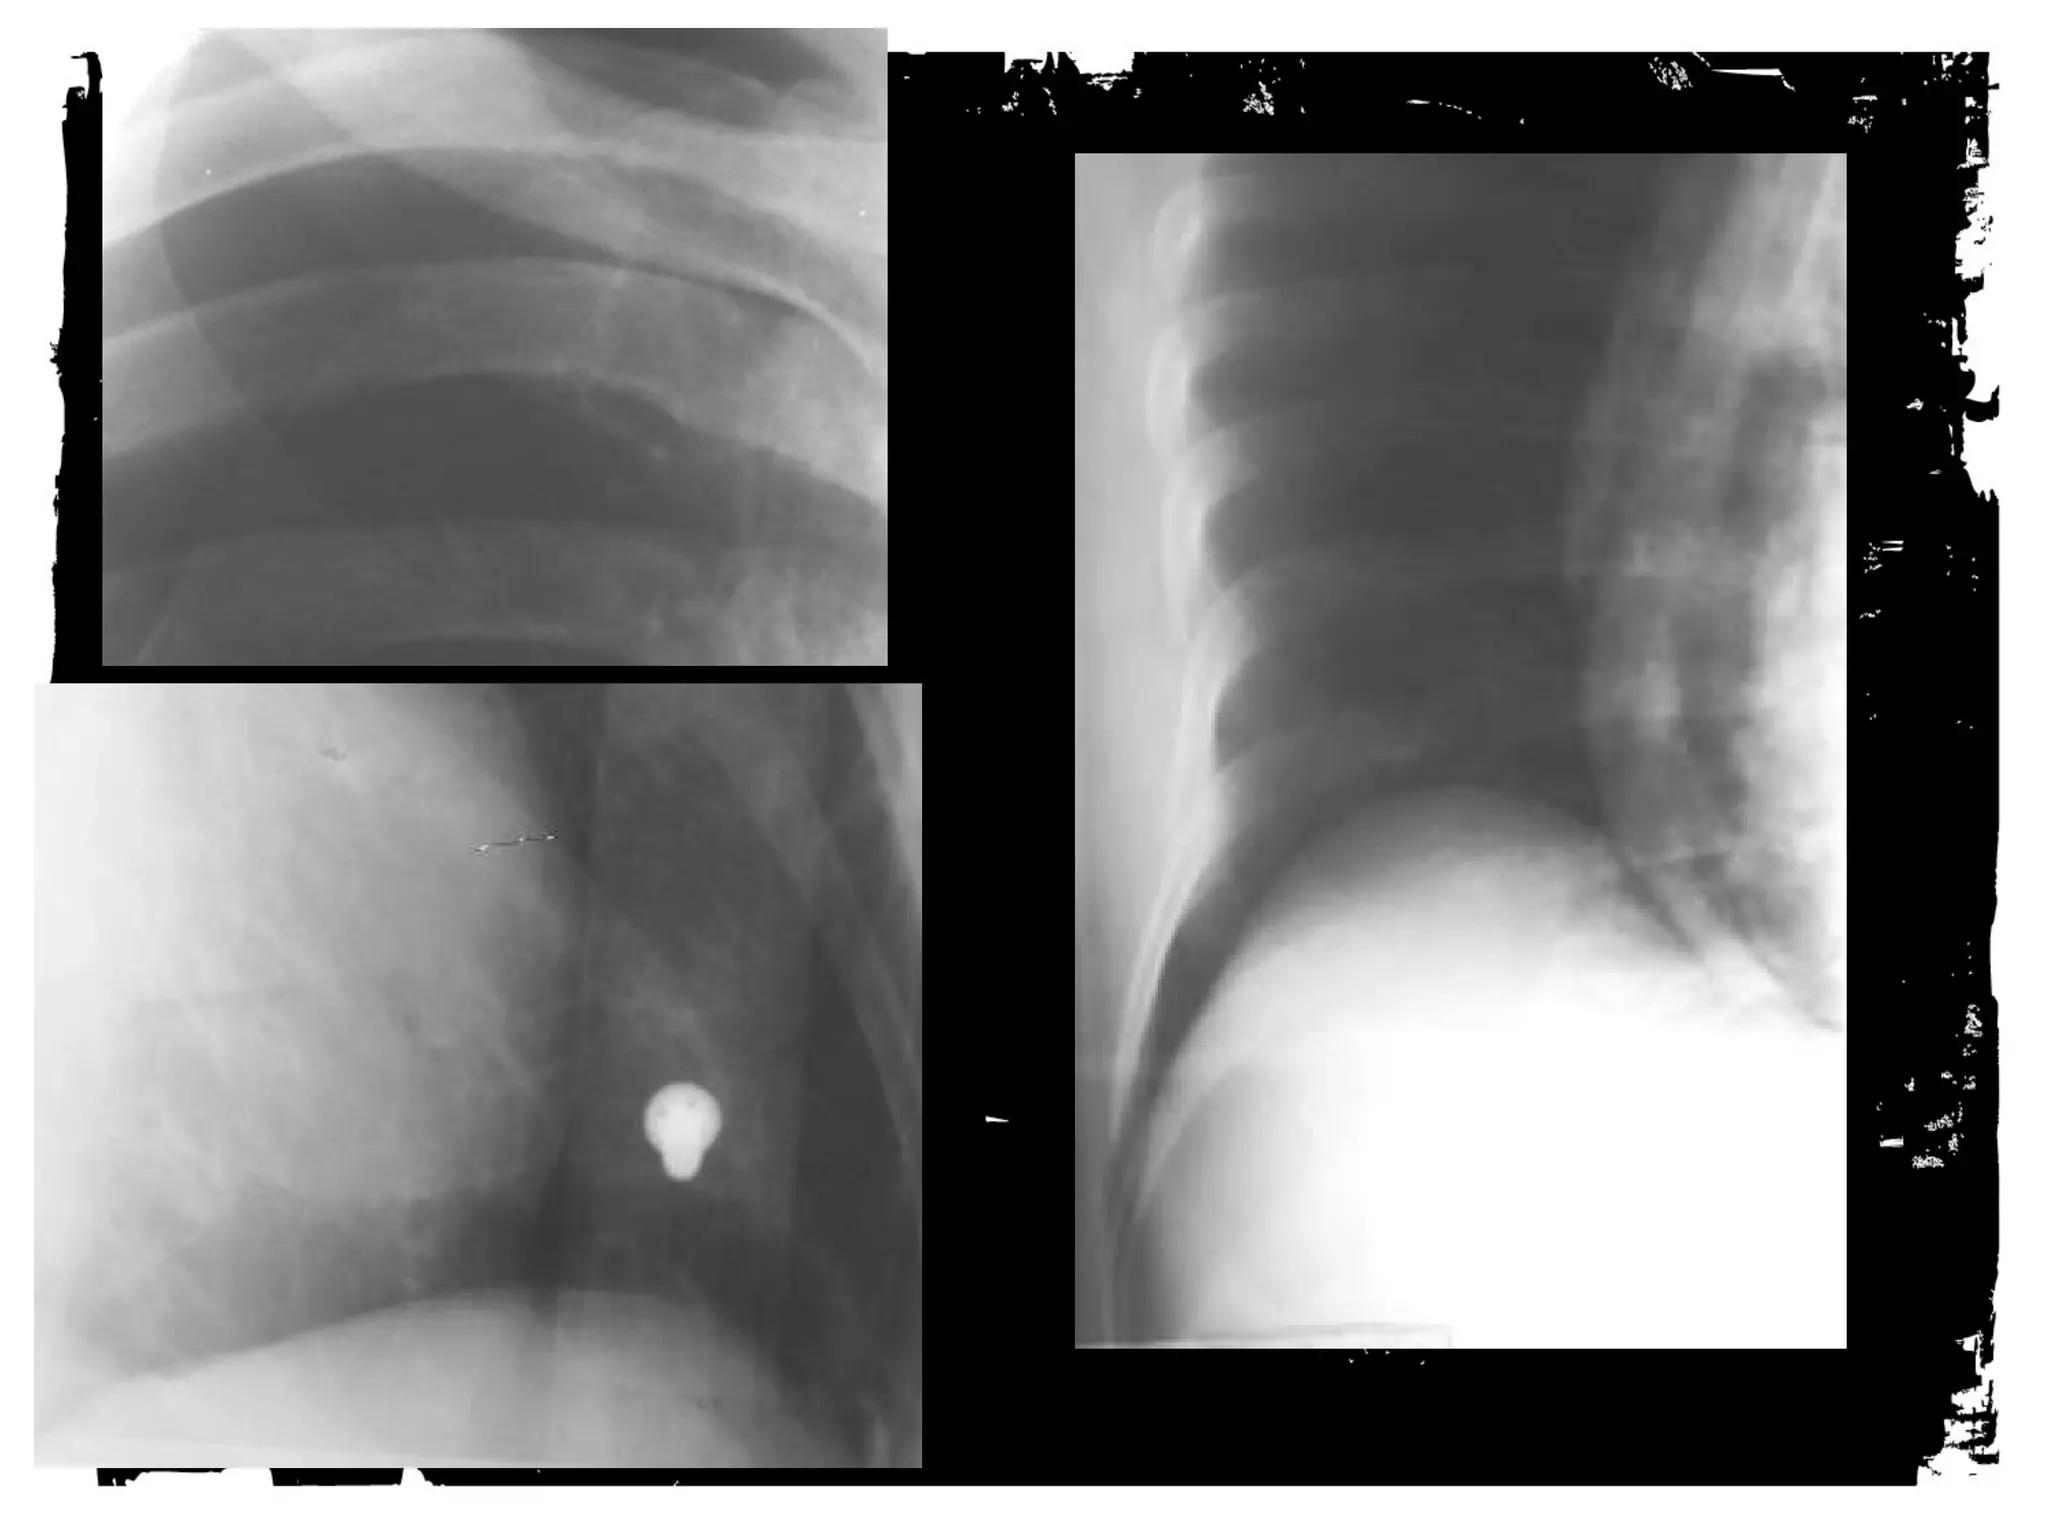

After chest trauma, imaging plays a key role for both,

the primary diagnostic work-up, and the secondary

assessment of potential treatment. Despite its well-known

limitations, the AP chest radiograph remains

the starting point of the imaging work-up. Adjunctive

imaging with CT, that recently is increasingly often

performed on MDCT units, adds essential

information not readily available on the CXR. This

allows better definition of trauma-associated thoracic

injuries not only in acute traumatic aortic injury, but

also in pulmonary, tracheobronchial, cardiac,

diaphragmal, and thoracic skeletal injuries.

• Spine Injuries

• Look for loss of

alignment, fractures and

paraspinal hematoma.

• The findings may be very

subtle.

DIAPHRAGM Injuries

• 5% of major blunt trauma,

also thoraco-abdominal

penetrating trauma

• Left clinically injured

more than right 60/40

• Sensitivity of Chest film

40%. CT better, but still

misses some

• Sure signs: NGT through

g.e. junction then up into

chest, and hollow viscus

above diaphragm

• Less significant signs:

Indistinct diaphragm,

effusion, atelectasis